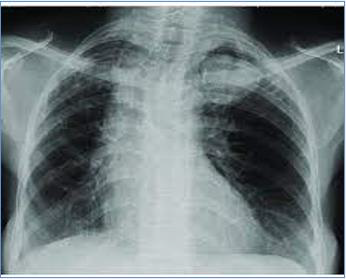

Aspergilloma (Fungus Ball)

Is the most common of the noninvasive pulmonary Aspergillus infections. That Aspergillus fumigatus takes up residence in a lung cavity produced by preexisting disease, particularly, tuberculosis, histoplasmosis and sarcoidosis. Aspergillus fumigatus multiple in lung cavity and produce a mycelial mass referred to fungus ball, Signs and symptoms may be absent for years, but in some cases blood vessels in the cavity wall lead to hemoptysis and hemorrhages that may be sever [3] (Figure 5 & 6 & 7).